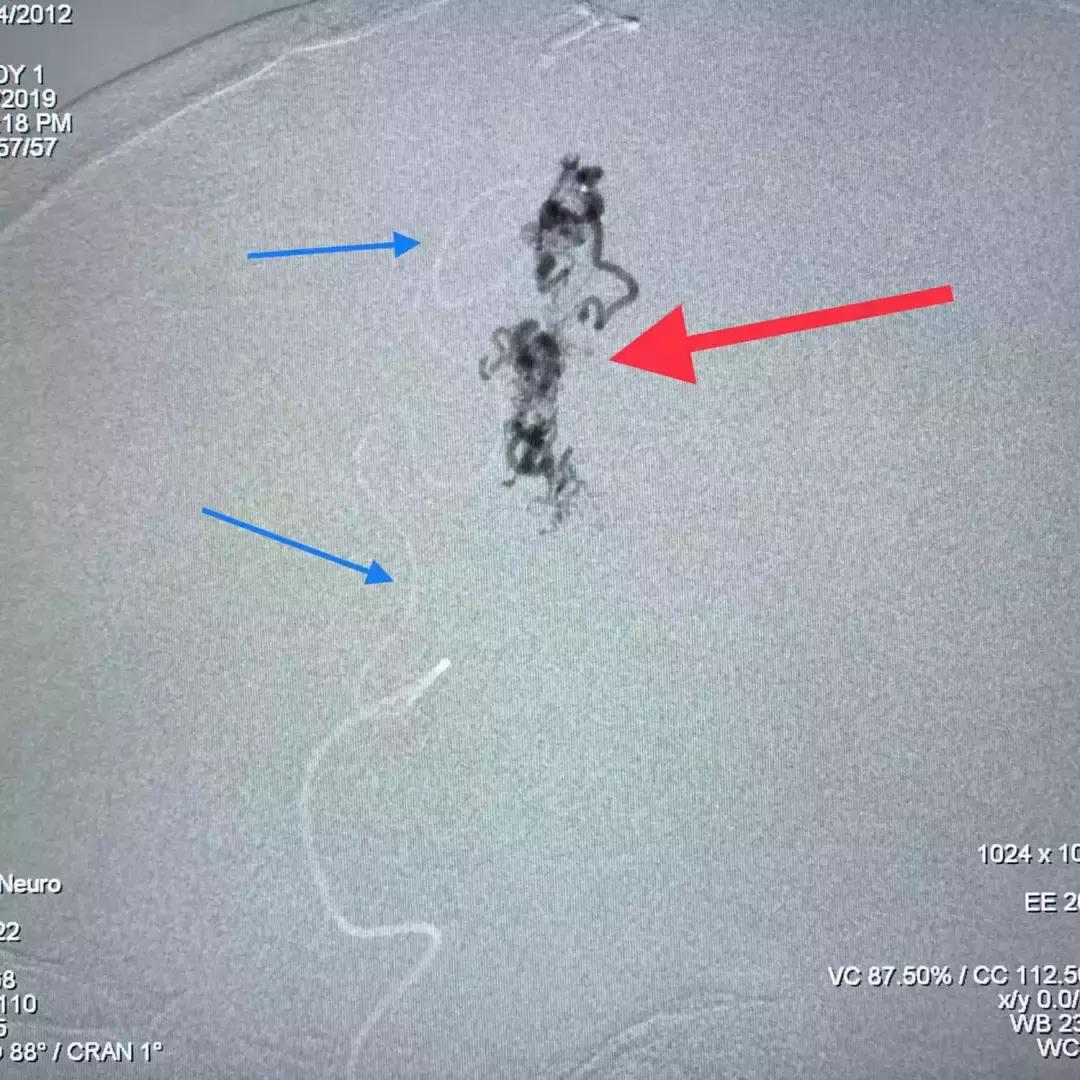

术中,刘加春教授通过这样的尝试锁定了两支动脉。如何注胶呢?由于血管结构原因,胶浓度不合适常常弥散不好,达不到畸形团“铸型”栓塞的效果。最后,刘加春教授决定采用稀释6倍的Glubran胶进行栓塞。

上图蓝色箭头为微导管的路径,可见多么曲折;红箭为胶在畸形团的铸型。